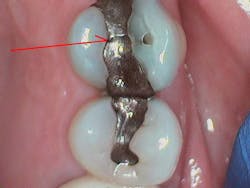

Case 2: Replacing amalgam, fractured tooth, undermined enamel

What began as a routine replacement of a fractured amalgam restoration (figure 8) developed into a larger restoration of a fractured tooth (figure 9). It is often difficult to know how much dentin remains when replacing old restorations. The amalgam restoration preparation undermined the buccal cusp enamel, resulting in asymptomatic vertical fractures of the pulpal floor (figure 9). Undermined enamel is not a concern when using glass ionomer restoratives, because there is no contraction shrinkage; the chemically fused zone is strongly bound and re-supports the enamel. A glass-hybrid (Equia Forte HT) was chosen due to its strength and similar coefficient of thermal expansion as well as the need to re-support the undermined enamel without causing “craze lines” often occurring in traditional light-cured composite restorations.

Figure 10 shows the final restoration. The ionic chemical bond of glass-hybrid (the chemically fused zone) to tooth structure will strengthen the tooth more than the previous mechanically retained amalgam.